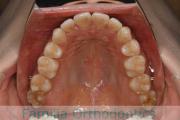

No.22V-299

- 上顎前突

- 叢生

- 30歳

- 女性

- 上:

- 44

- 下:

- 主な使用装置:

- FEA 022

- 治療にかかった費用:

- 90万円

上の出っ歯、口が閉じにくい、下の前歯のガタガタを治したいということで来院されました。上顎から左右小臼歯を、下の前歯は凹凸が非常に強いので、こちらから一本抜歯を行いました。2年強、30回程度の通院が必要でした。

成人になってからの叢生(でこぼこ、凹凸、ガタガタ)は、保定をしっかりしないと後戻りをしてしまうリスクが高いです。